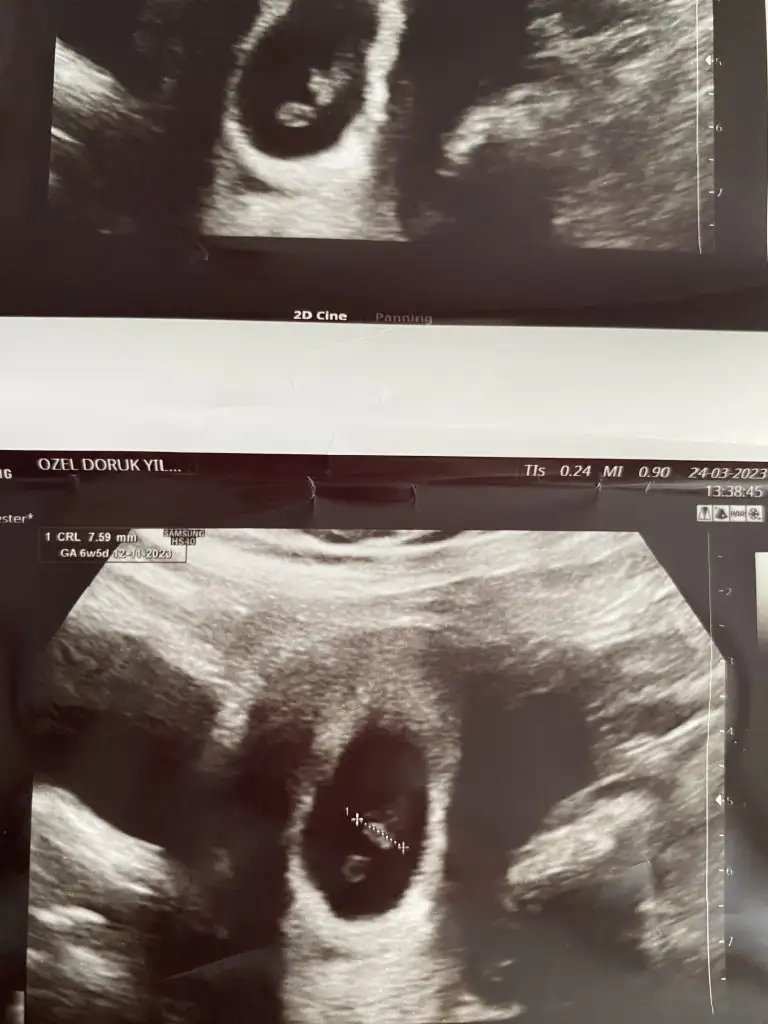

Karından ultrason bu arada

plesantası sağda bu yüzden kız aşkım :D

melegim can melegim can kız dedı :D bende ramzı teorısıne gore plesanta sağda ıdı oyuzden kız dedım D: bakalım tutacakmı melegım pozıtıfbırınde de tutturmustu :D